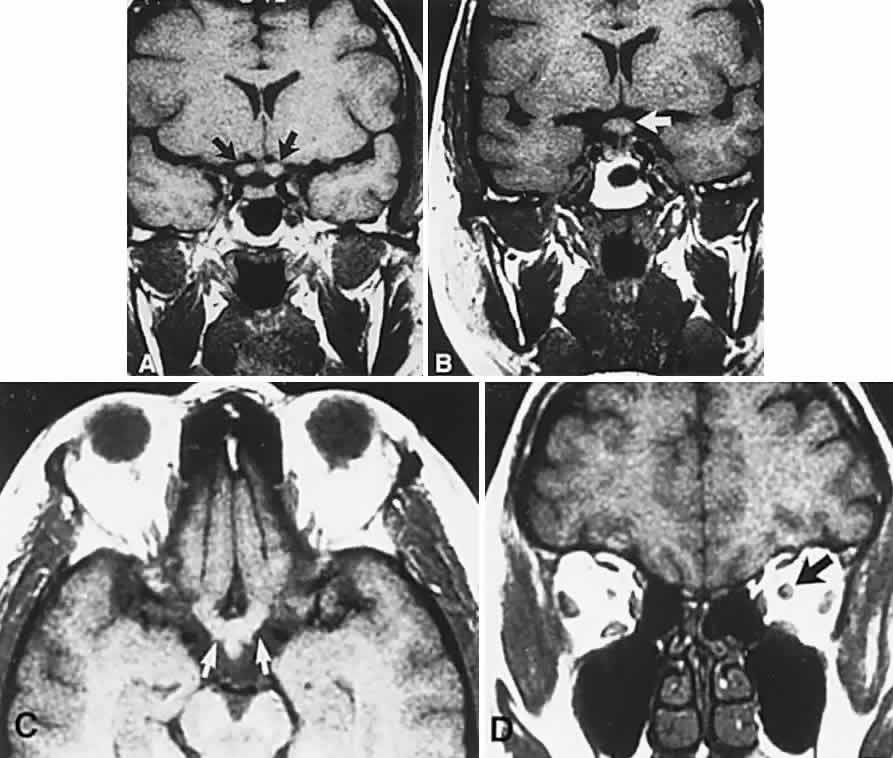

Fig. 2. Large prolactinoma. Original vision in the right eye (RE) was 8/200, left eye (LE) 1/200, with serum prolactin of 26,000 ng/ml and galactorrhea. Four months of bromocriptine reduced prolactin to 661 ng/ml, vision improved to RE 20/40, LE 20/50. At 3 years, vision was as follows: RE 20/30, LE 20/20; prolactin was 25.9 ng/ml. Enhanced magnetic resonance imaging. Sagittal (A) and coronal (C) images at diagnosis. Sagittal (B) and coronal (D) images at 2-year follow-up, showing dramatic shrinkage of the mass.

Fig. 4. Magnetic resonance imaging of a suprasellar meningioma (TR, 600 milliseconds; TE, 20 milliseconds). A. Coronal section of a large meningioma (large arrows), isodense to brain. B. Sagittal section. Note the normal sella and pituitary gland (p). Sagittal (C) and coronal (D) sections of a planum meningioma, extending into the sella. Note the upward deflection of the chiasm (arrow in C) and extension to the cavernous sinus (arrows in D).